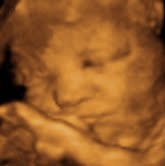

Thought I'd share 2 pics- 33w 3D sono and 10 days old

I got the 3Ds done at impact. We actually went 3x- once for an early gender determination and twice (at 24w and 33w) just for pics etc.

Here is a comparison shot of the 33w and Luca at about 10 days old.

I thought u guys would like to see  Image Attachment(s):